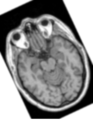

• Retrieved a 2D Slice from Slicer and automatically ran it through a small workflow